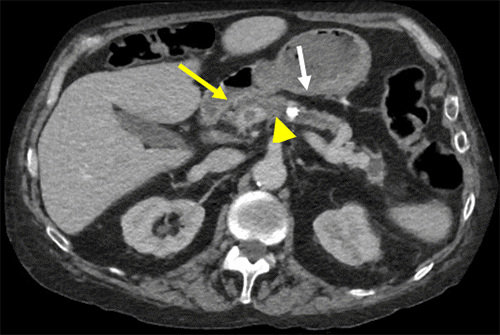

Magnetic resonance imaging (MRI) of the right lower extremity showed findings consistent with noninfectious osteomyelitis—diffuse soft tissue edema around the right ankle with effusion, fluid in the posterior tibialis tendon sheath with synovial and muscle enhancement, and osseous hyperenhancement of the mid-tibial shaft with periosteal edema (Figure 2). Computerized tomography (CT) scan of the abdomen and pelvis with IV contrast was notable for soft tissue stranding around the pancreatic head, a large pancreatolith in the body of the pancreas, and a non-occlusive superior mesenteric vein (SMV) thrombus (Figure 3). MRI of the abdomen demonstrated pancreatic ductal dilation and a focal area of pancreatic necrosis in the uncinate directly adjacent to the SMV (Figure 4).

Figure 3. A) Axial and B) Coronal Images of Body and Tail of Pancreas. Published with Permission

A.

Scans demonstrate a pancreatolith (white arrow) with upstream pancreatic duct dilation and focal pancreatic necrosis (yellow arrow). There is a small thrombus located in the adjacent SMV (arrowhead)

B.

Scans demonstrate a pancreatolith (white arrow) with upstream pancreatic duct dilation and focal pancreatic necrosis (yellow arrow). There is a small thrombus located in the adjacent SMV (arrowhead).